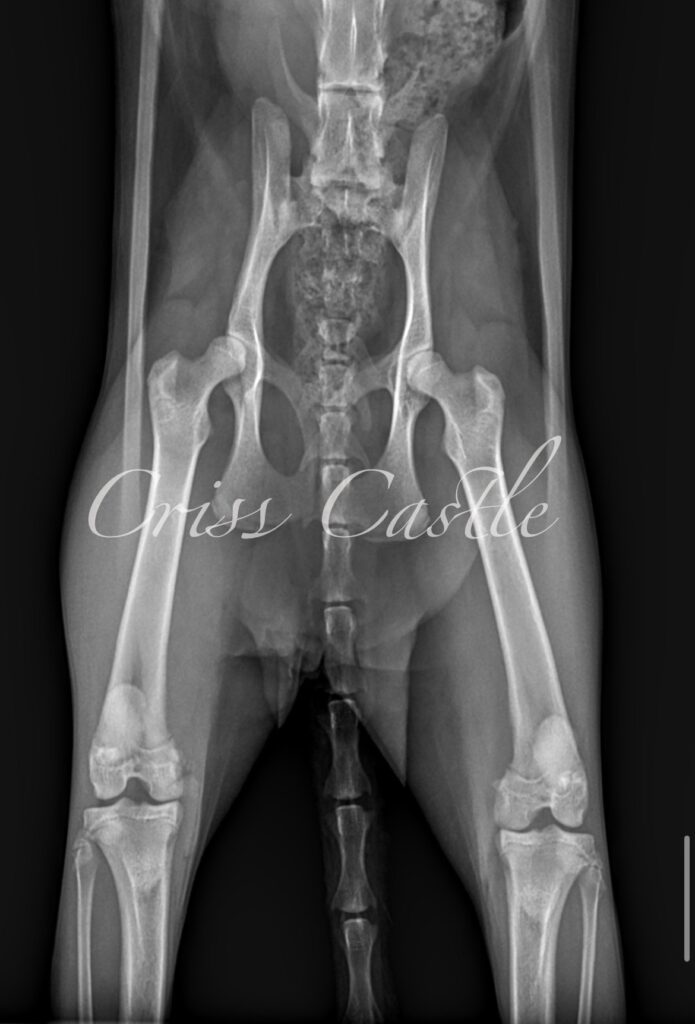

Hip X-Ray Results

Below are the current hip x-ray results for each Criss Castle breeding cat.

Note that as the cats continue to grow, this page may be updated with new results.